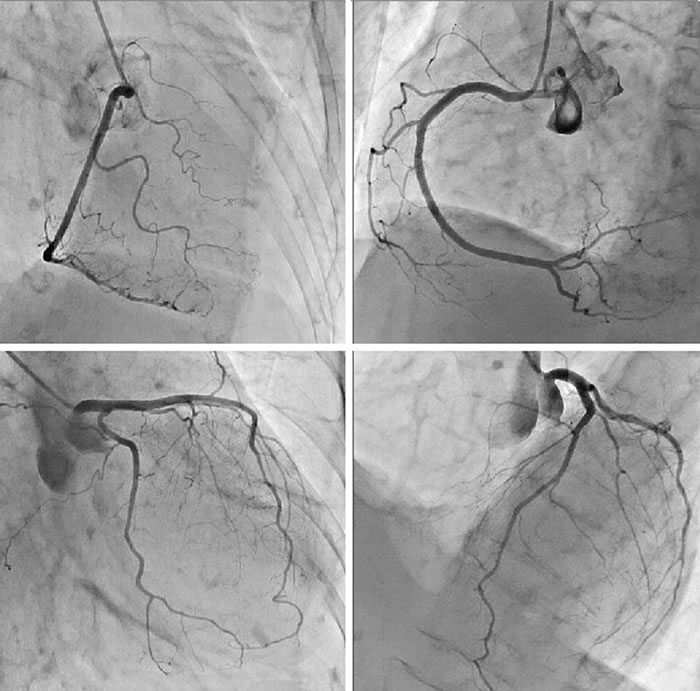

正常な冠状動脈の造影像の例(上左図:右冠動脈を右前斜位より見る 上右図:右冠動脈を左前斜位より見る 下左図:左冠動脈を右前斜位、下方寄り見る 右下図:左冠動脈を左前斜位、上方より見る)

心臓カテーテル検査の中で、冠動脈造影は最も重要なものの一つです。冠動脈造影は、虚血性心疾患(狭心症・心筋梗塞)を疑われる患者さんにとっては、その最終診断、治療方針の決定に欠かせない重要な検査です。

冠動脈は入り口の異なる左右の2本からなります。左冠動脈は、入り口からすぐに左前下行枝と左回旋枝という大きな枝にわかれるので、これをそれぞれ独立に数えて、『冠動脈は3本ある』と言われます。左冠動脈の根本の部分は別個に左主幹部として扱われます。冠動脈に限らず血管は普通のX線写真では描写できませんから、造影剤(胃の検査で使うバリウムのようなもの)が必要になります。

これを冠動脈に直接注入するための細いチューブをカテーテルと言います。このカテーテルを足の付け根や肘の動脈から冠動脈まで進めて、注射器で冠動脈に造影剤を流します。 冠動脈が途中で狭くなり、心筋に十分血液が供給されなければ狭心症、閉塞して供給が途絶えると心筋梗塞に陥ります。この検査結果をふまえて、薬物療法、カテーテルによる治療、外科的な冠動脈バイパス術のどれが治療に適しているか、決定されます。